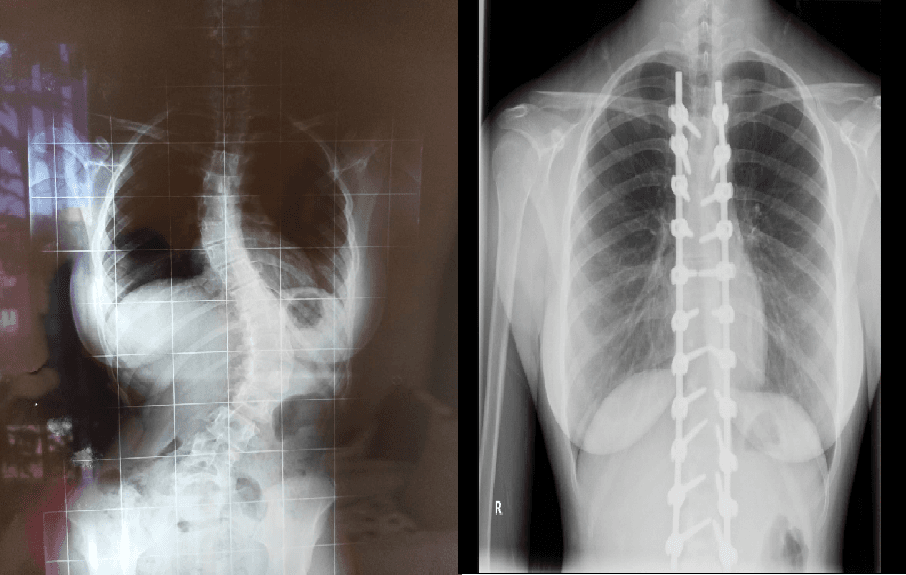

Buraya kadar çok zor ve belki de korkutucu gerçeklerden bahsettim ancak ameliyata girip çıktıktan, ailem beni saatlerce ameliyathanenin önünde bekledikten sonra her şey bambaşka oldu. Ameliyatım başarıyla tamamlandıktan sonra, ailem beni görmeden önce doktorum sayesinde röntgenlerimi gördüler ve anlattıkları kadarıyla gözlerine inanamadılar. Çünkü çok yüksek derecelerdeki eğrilikler yok olmuş, neredeyse sıfırlanmıştı, ameliyatta hiçbir komplikasyon oluşmamış ve beklediğimizden daha başarılı geçmişti. Omurgama yerleştirdikleri implantlar artık yeni en yakın arkadaşlarım olmuştu. Narkozun etkisi geçmeye başlarken ailemin yanına getirildim ve ilk olarak kollarımı bacaklarımı hareket ettirmemi izledik. Belki günlük hayatımızda farkında olmadan yaptığımız bu küçücük hareketler o sırada bizim için tüm dünyaya bedeldi. Hareket edebiliyordum. Yürüyebilecektim. Birkaç günlük yatak istirahatinden sonra ayağa kalktım. Sanki 13 yıl boyunca hiç yürümemiş gibi hissediyordum çünkü vücudumun bütün dengesi değişmişti. O gün 13 yıl sonra yeniden yürümeyi öğrendim. Tıpkı bir bebeğin ilk adımları gibi, tek başıma ilk adımlarımı atmayı öğrendim.